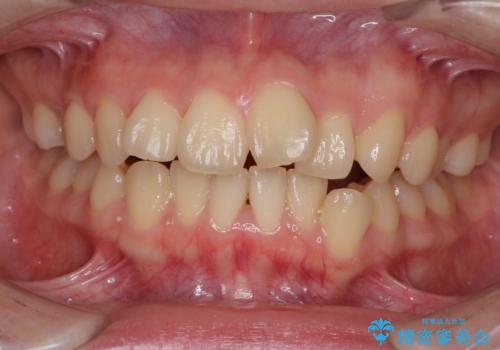

- デコボコと飛び出した前歯を治したいとのことで来院された患者様です。

ゴムかけを活用して上顎歯列全体を後方移動し、IPR(歯と歯の間を削る)によってデコボコが解消するように設計し、インビザラインにより治療を行うこととしました。

後方移動に際し、上下顎の親知らずは4本とも抜歯することとしました。